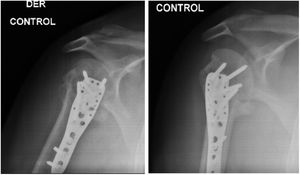

Reporte de casoMasculino de 35 años de edad quien ingresa al servicio de urgencias tras sufrir accidente de tránsito en motocicleta ocasionándole trauma en hombro derecho y rodillas bilaterales. Rayos X de ingreso se observa luxo fractura multifragmentada en 4 partes (Neer IV) en hombro derecho y fractura de platillos tibiales derecho (schatzker IV) (fig. 1), estatus neurológico normal, sin déficit neurovascular. Fracturas de manejo quirúrgico.

Fue inmovilizado con cabestrillo durante el primer mes. Inició fisioterapia al mes siguiente de su intervención quirúrgica trabajando manejo del dolor y edema, recuperación de la movilidad articular, fuerza de la extremidad y actividades básicas cotidianas, el paciente solo logró realizar 20 sesiones de fisioterapia. Cada mes se realizó rayos x de control (fig. 4) con evaluación por parte de ortopedia mostrando buena evolución. A los 6 meses post quirúrgico el paciente muestra evolución satisfactoria (figs. 5 y 6). Dolor leve a las rotaciones clasificado en 1 según escala análogo del dolor, movilidad articular: eleva hombro a 140°, abducción de 115°, rotación externa 20° rotación interna hasta T12. Consolidación de la fractura satisfactoria sin déficit neurovascular, con una puntuación en cuestionario DASH de 1.6